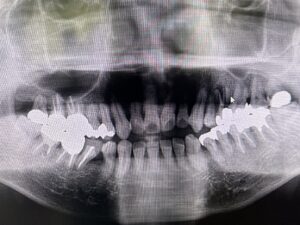

🔶初診時🔶

正面

噛んだ時に前歯にスキマがある

オープンバイト 日本語で かいこう

を気にして

マウスピース矯正希望で来院

この歯並びは歯に有害で

奥歯だけガシガシ当たるので

100%中年期で奥歯が割れて歯を失う事に

初診で来院時

すでに矢印の歯が割れていて

矯正後インプラントを予定